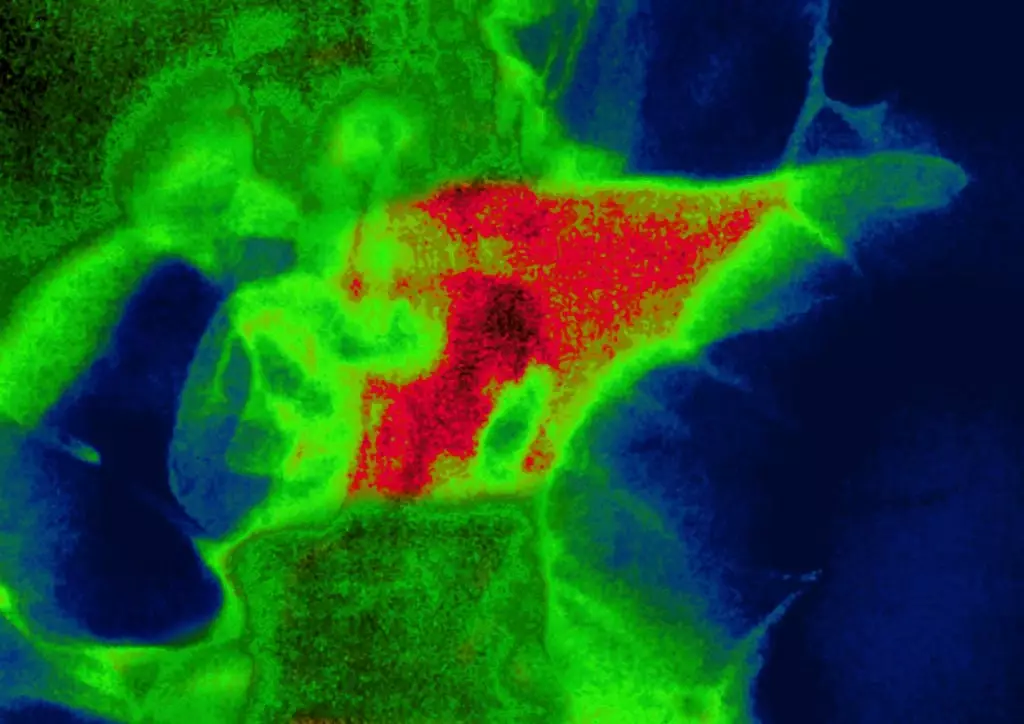

They've said there's a 'small risk of severe acute pancreatitis' for people taking these drugs, with it being a very rare side effect where a person's pancreas becomes swollen.

Most people with this get better by themselves, but in more serious cases, there can be complications which result in stomach pain, nausea and vomiting.

In the most serious of cases it can even be fatal by causing multiple organ failure, with the NHS warning that one in five cases falls into the severe category which leads to complications the worst of which being death.